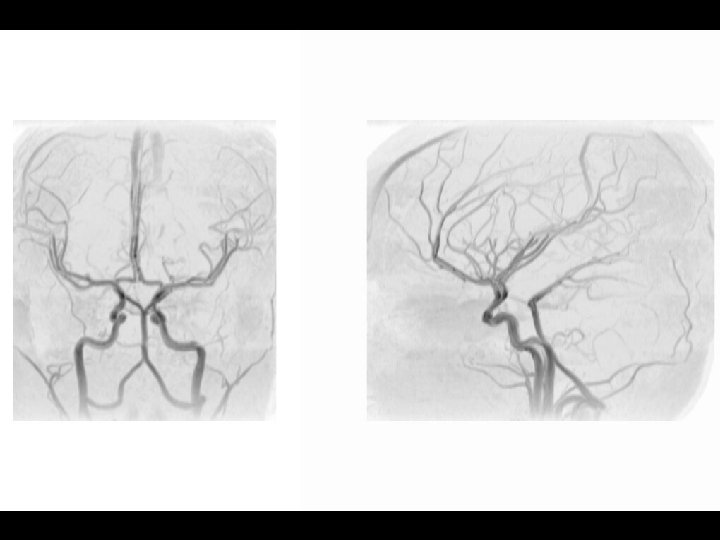

Arterial Blood Supply

Anterior circulation Internal carotid arteries Posterior circulation Vertebral arteries